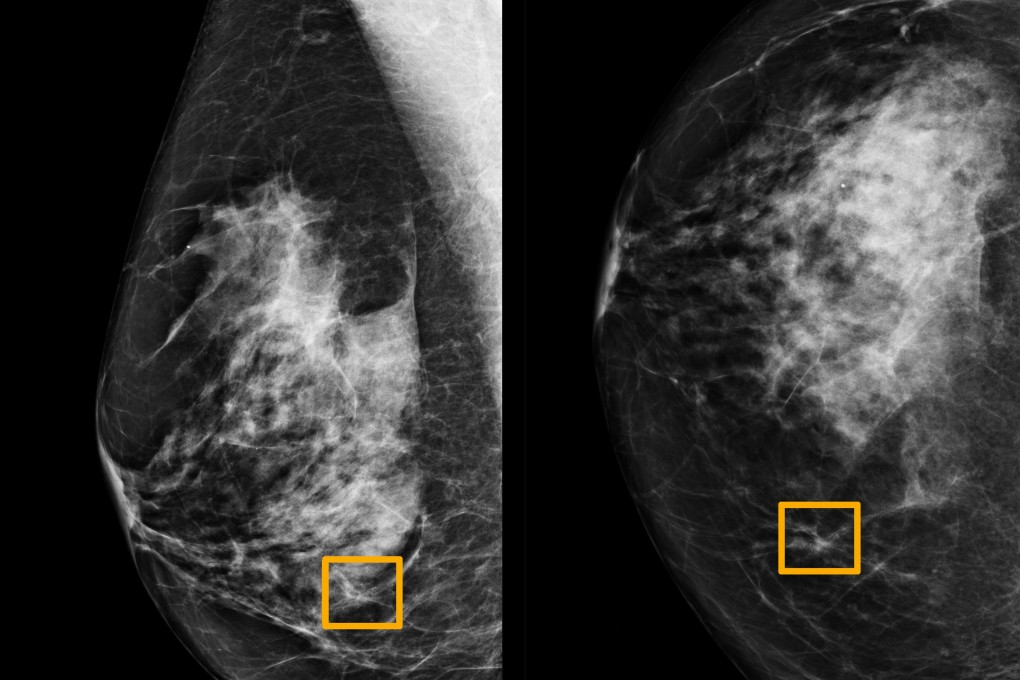

Google AI system could detect breast cancer at least as accurately as expert radiologists, study finds

A Google artificial intelligence system proved as good as expert radiologists at detecting which women had breast cancer based on screening mammograms and showed promise at reducing errors, researchers in the United States and Britain reported.

Radiologists miss about 20 per cent of breast cancers in mammograms, the American Cancer Society says, and half of all women who get the screenings over a 10-year period have a false positive result.

The team, which included researchers at Imperial College London and Britain’s National Health Service, trained the system to identify breast cancers on tens of thousands of mammograms.